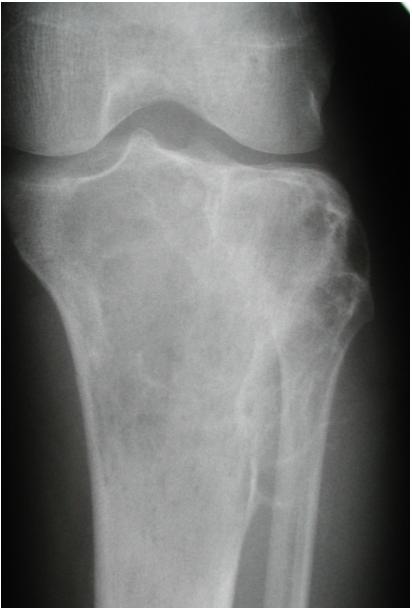

Aneurysmal Bone Cyst

site: Distal tibial

size: Involving most of distal part

matrix: Cortical expansion, radiolucent matrix, well defined, narrow zone of transition

soft tissue involvement: no peristeal reaction